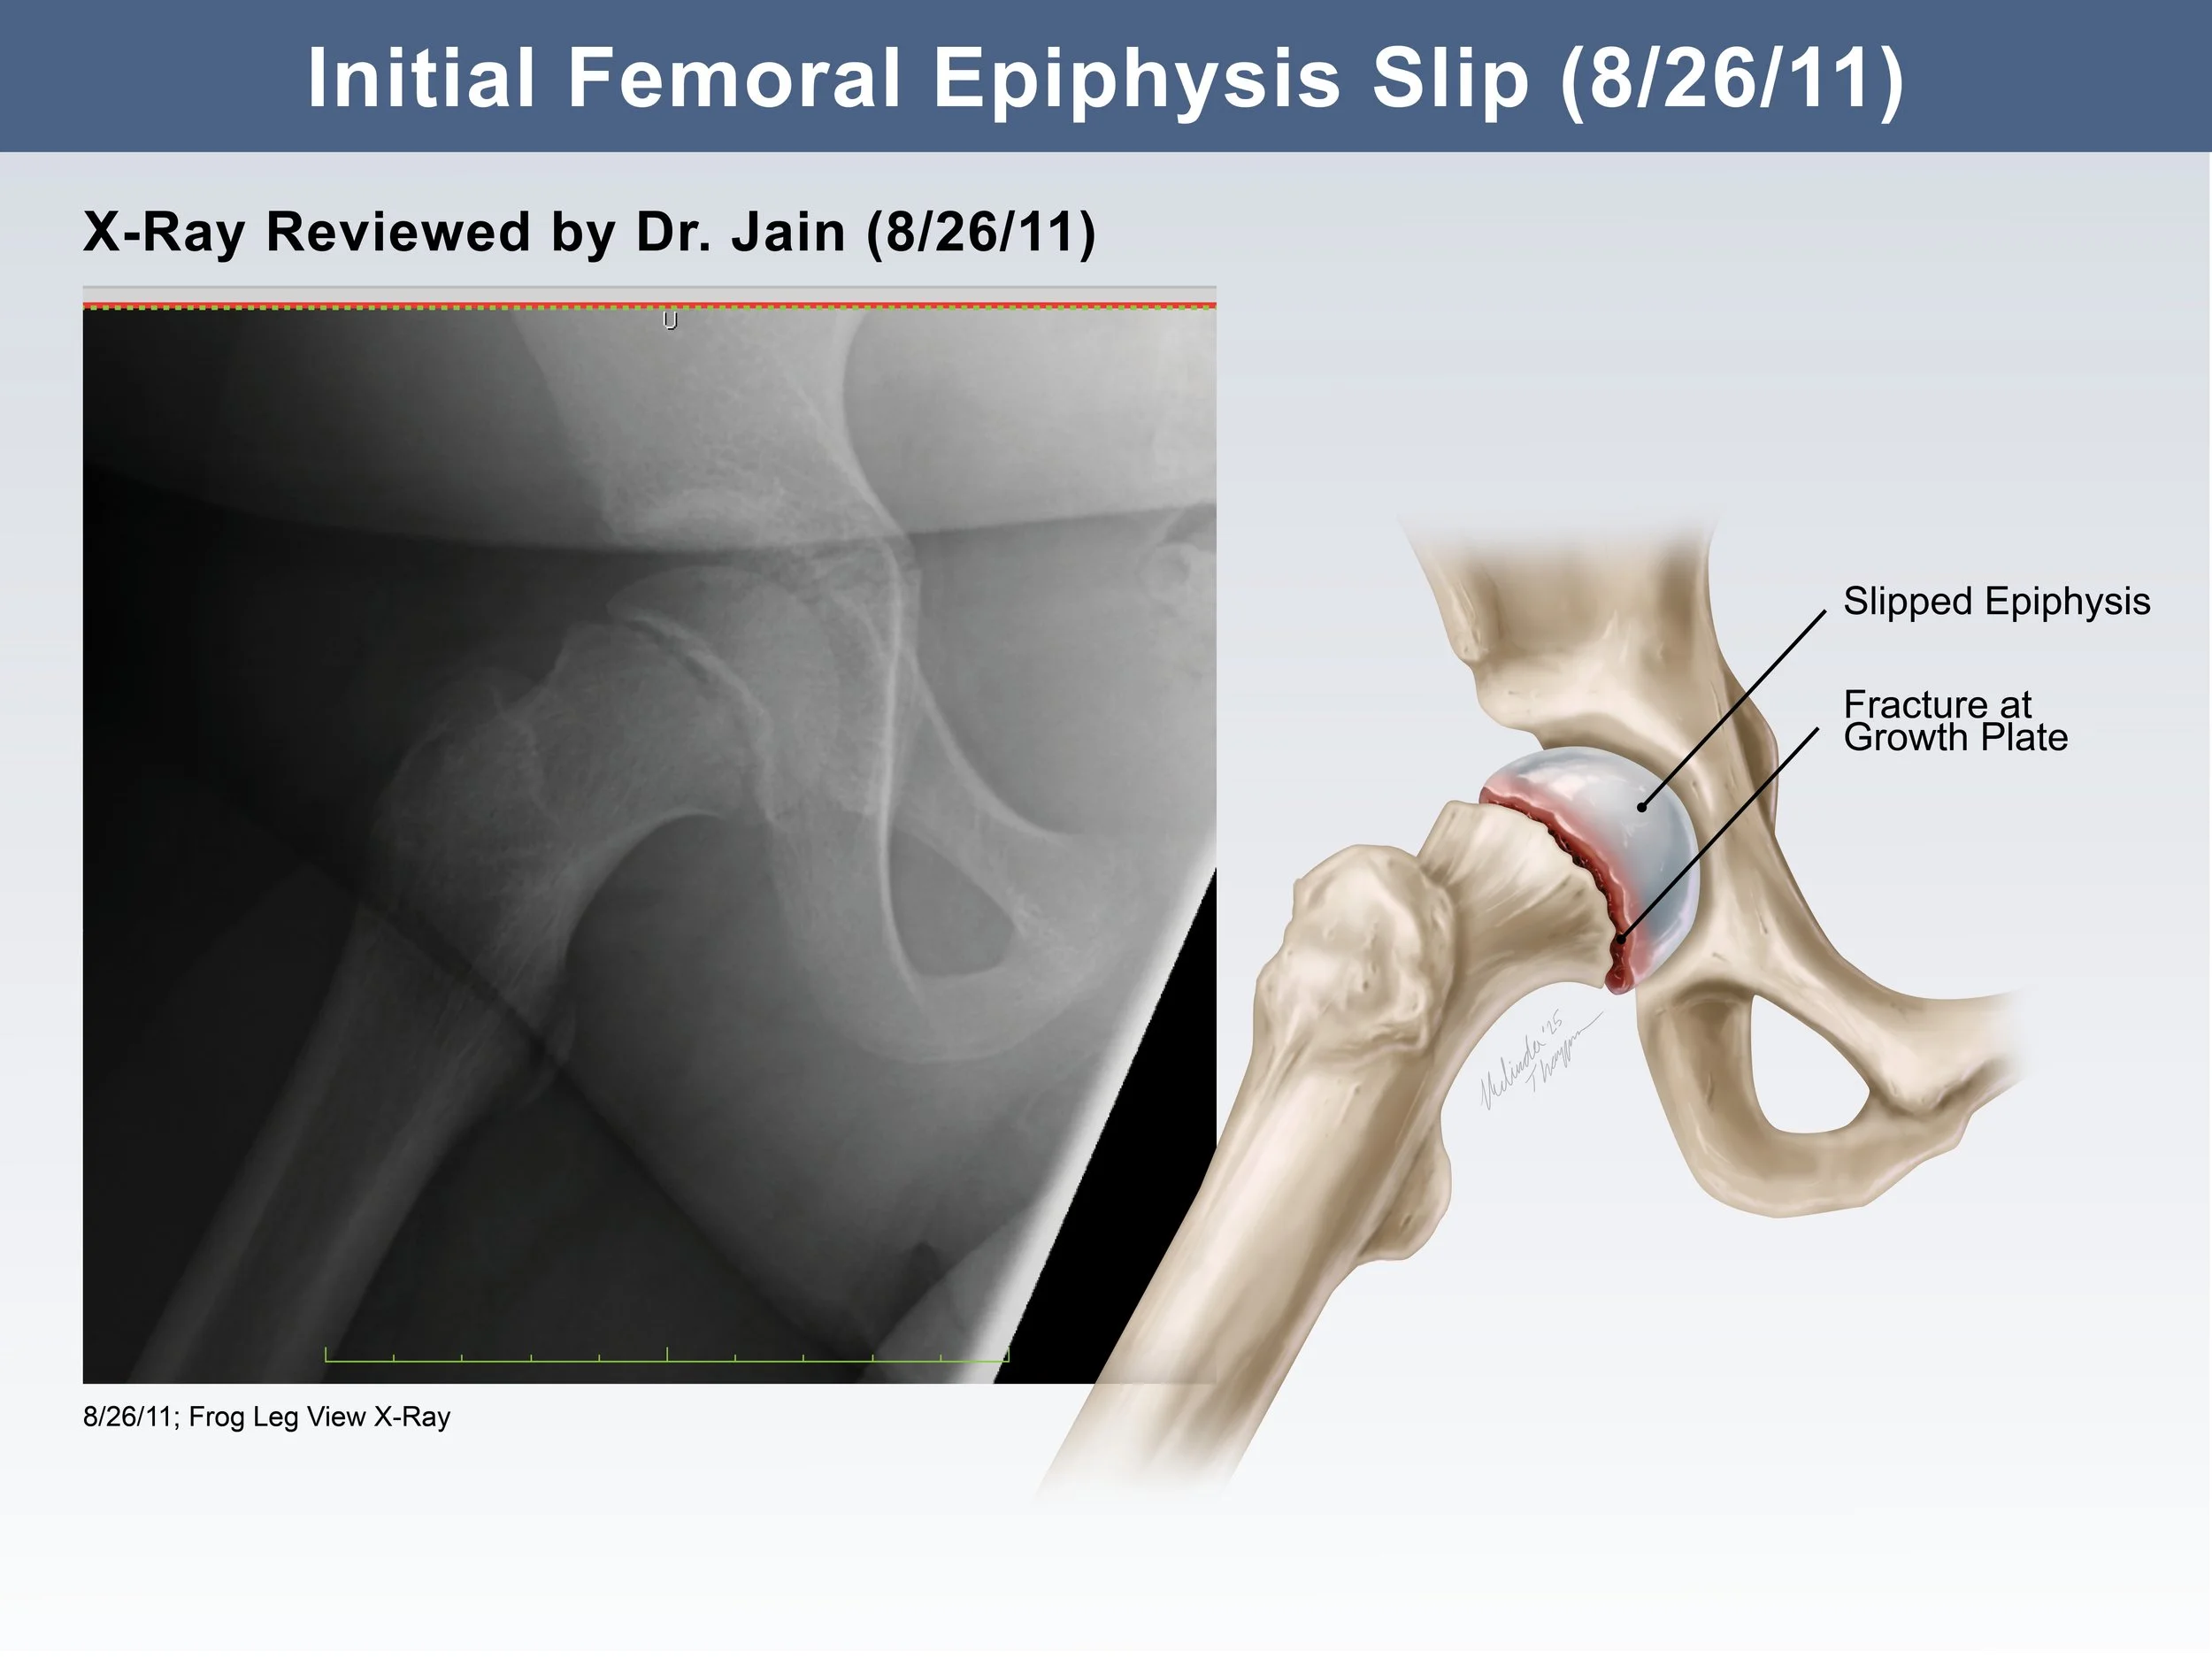

Medical Legal Illustration

Medical Illustration is important in the courtroom for many reasons including communicating scientific information for a lay audience, highlighting injury or anatomical differences, or simply representing potentially disturbing images in a more digestible way. Legal illustrations must be accurate, but still serve to help tell the defendant or plaintiff’s story.

SCFE Exhibit Design

These illustrated slides were created for a medical legal illustration course to accompany the plaintiff’s case in a “mock trial” presentation. The illustrations show the the progress of a slipped capital femoral epiphysis fracture (SCFE) that ultimately led to disability in a young girl. The illustrations were used to clearly communicate x-ray information to a lay audience and demonstrate why the doctor’s misread was easily avoidable. Additionally, the illustrations show the progression of symptoms as a result of that first missed diagnosis.

Adobe Photoshop, Indesign